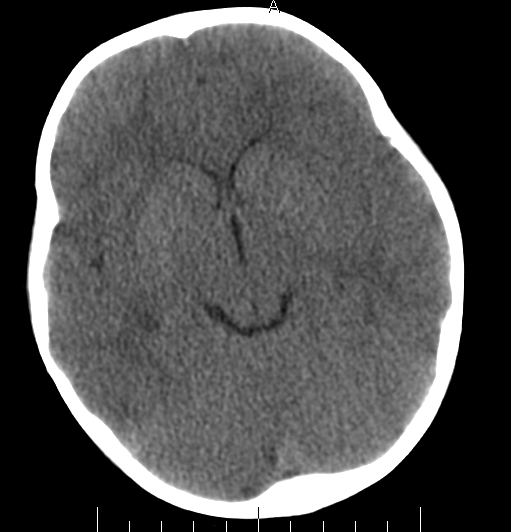

女,3岁,头部外伤一小时。半卵圆中心低密度是什么意思,病灶?侧脑室?请指教。

正常表现

脑白质

幼儿正常脑白质表现,长期观察,必要时mr

从层面看不是侧脑室,考虑低密度变,建议mri。

不是侧脑室,考虑正常脑白质。为慎重,建议mr!